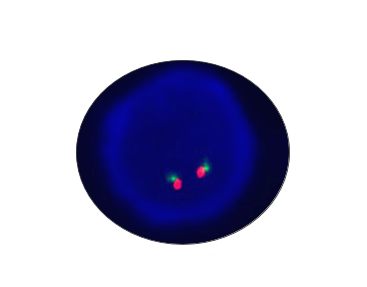

ROS1 Breakapart

Probe Description: ROS1